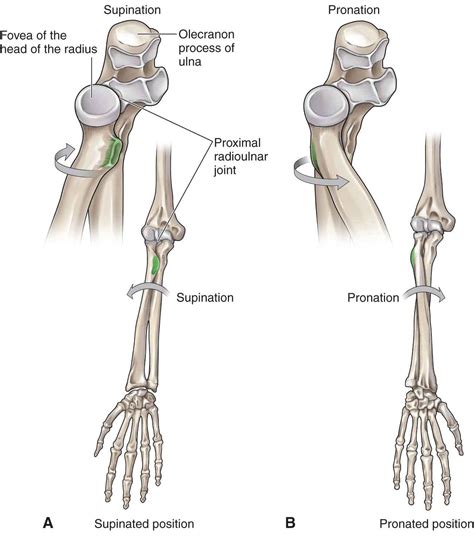

The Proximal Radioulnar Joint is a pivot joint that connects the proximal end of the radius to the ulna. This joint is stabilized by several ligaments, including the annular ligament, which encircles the radial head and holds it in place against the ulna. The joint capsule and surrounding muscles also contribute to its stability and function.

The PRUJ is part of the complex elbow joint, which includes the humeroulnar and humeroradial joints. Together, these joints allow for a wide range of movements, including flexion, extension, supination, and pronation. The PRUJ specifically enables the forearm to rotate around its longitudinal axis, which is crucial for activities like turning a doorknob or using a screwdriver.

The primary function of the Proximal Radioulnar Joint is to facilitate forearm rotation. This movement is essential for various activities that require the hand to be turned palm up (supination) or palm down (pronation). The PRUJ works in conjunction with the distal radioulnar joint to achieve these movements smoothly and efficiently.